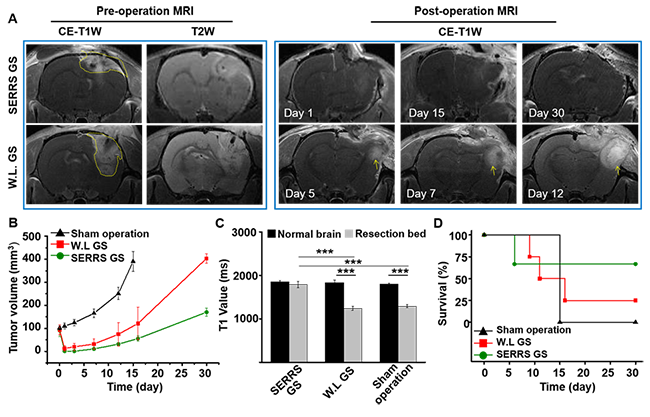

本工作开发了一种具有特征拉曼双峰的表面增强共振拉曼(SERRS)探针,其具有极高灵敏度和肿瘤特异性聚集,静脉注射后实现较强的信噪比。在小鼠脊背皮窗模型中,该探针选择性进入胶质瘤模型边缘区域,其拉曼信号在肿瘤边界区域达到最强并随肿瘤边缘距离的增加而逐渐减弱。在大鼠原位胶质瘤模型中,该探针经尾静脉注射后其特征双峰可通过手持式拉曼检测器清晰指示。在特征拉曼特征峰指导下,实现肿瘤组织的逐步切除直至检测不到探针信号。本工作还在大鼠脑胶质瘤模型上进行术后复发评估。SERRS导航可显著降低肿瘤复发率,延长大鼠整体生存期,动物模型平均生存率较白光导航组提高了50%以上。此外,这一工作同时提示,SERRS探针结合手执式拉曼仪的高灵敏手术导航技术对其他浸润性肿瘤的手术精准切除同样具备应用潜力。

图四:SERRRS引导大鼠脑胶质瘤切除提高手术预后